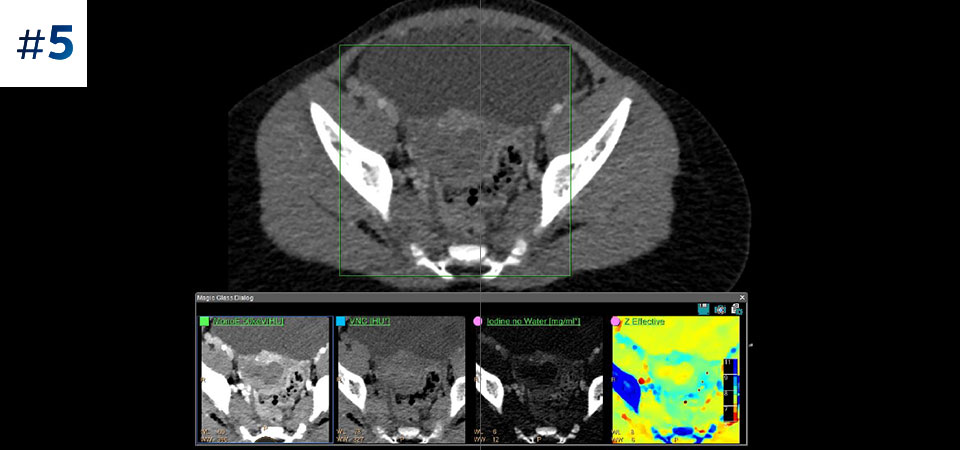

Masse au niveau du cou